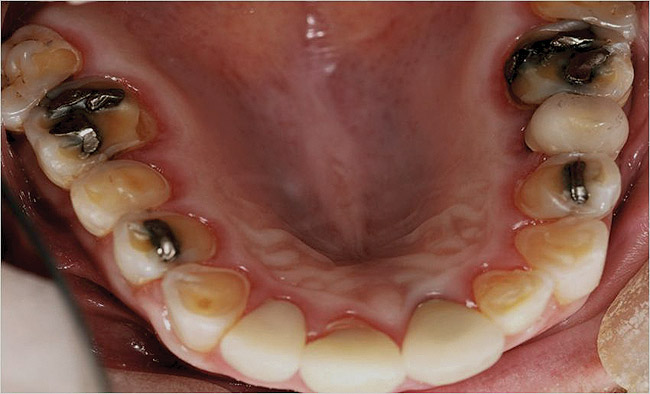

Figure  2  Loss of tooth surface surrounding amalgam and appearance of the restoration protruding from the tooth surface.

Figure 2